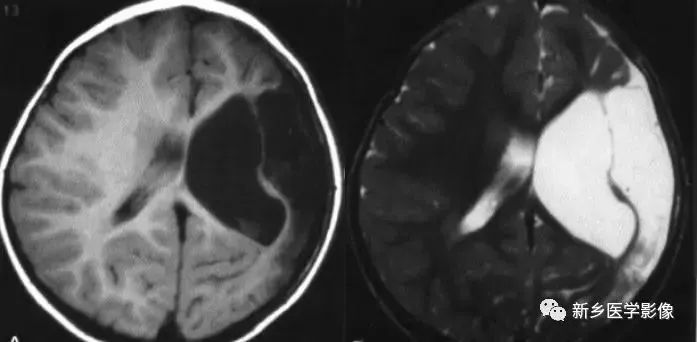

侧脑室局部扩大

❶ 局限性脑萎缩

外伤后脑萎缩、感染后脑萎缩、脑梗死后脑萎缩:

CT可见扩大的脑室部分附近的脑实质呈片状低密度灶;MR可见T1WI呈低信号,T2WI呈高信号。同时脑沟及蛛网膜下腔增宽。

❷ 侧脑室神经上皮囊肿

通常位于侧脑室三角区,囊壁薄,通常显示不清。由于囊内含脑脊液,所以CT及MR都表现为脑脊液信号。